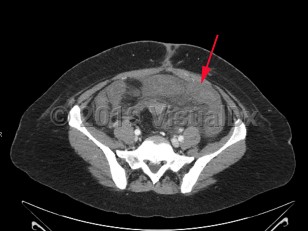

Acute mesenteric ischemia is a sudden interruption or severe reduction in blood flow to the bowel leading to ischemia, necrosis, and ultimately perforation. It is a medical emergency requiring emergent intervention to restore perfusion, often requiring a multidisciplinary approach. Mesenteric ischemia can result from several distinct pathologic entities including embolic disease, arterial thrombosis, mesenteric vein thrombosis, and lack of perfusion due to low flow states or nonocclusive mesenteric ischemia (NOMI).

Mesenteric ischemia is relatively rare with an incidence of roughly 5-8 per 100 000 per year. The incidence of mesenteric ischemia increases significantly with age, with a median age at presentation of 67 years. While advancements in treatment strategies have made significant improvements in the mortality of mesenteric ischemia, it remains high at approximately 50%. As with overall incidence, mortality increases significantly with age.